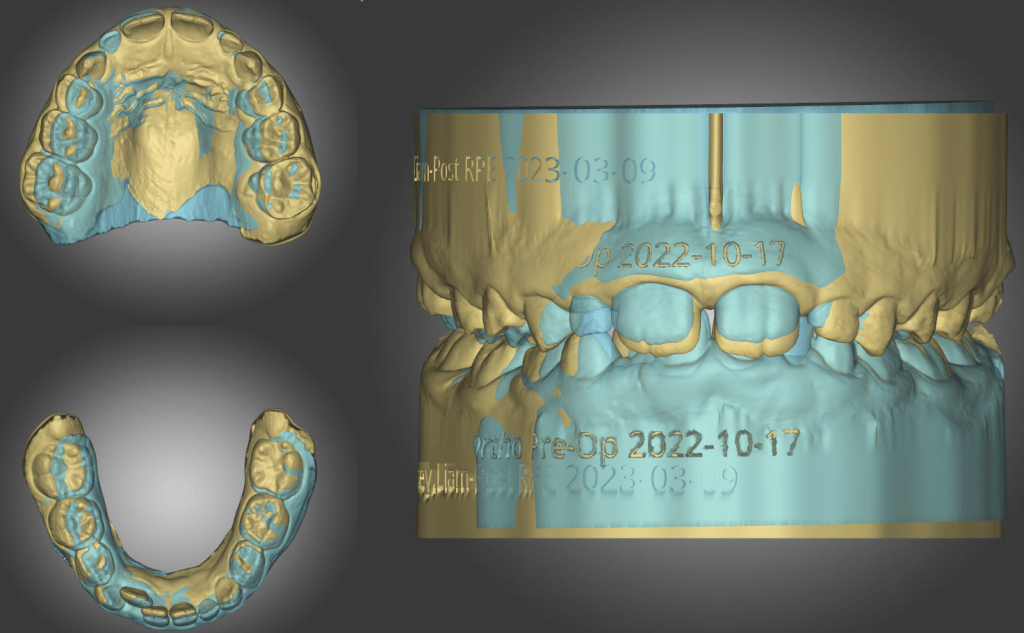

Once the case has started patient, motivation must be maintained and if not the result will be compromised. The key is monitoring and communication. Periodic progress scan and review gives both the patient and the clinician impetus during the course of treatment.

- orthodontic software to plan movement

With experience and careful planning the clinician becomes more confident of delivering great clinical outcomes consistently. Having just the first two components, the digital scanner and the software, would already give the clinician the advantage of control over the case compared to using a third party provider.